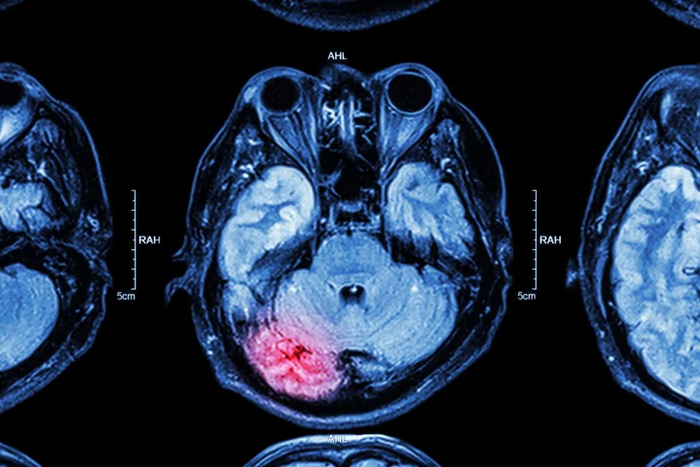

描述“植物人”的术语是持续性植物状态(Persistent vegetative state,缩写PVS)。通俗地说,所谓的植物状态指的是,由于各种原因造成脑严重损伤后出现的一种缺乏意识内容的觉醒状态,患者的语言、思考等一系列高级大脑功能统统丧失了,可有自发性或反射性地睁眼,也可有自发地无意义哭笑,对疼痛刺激有回避反应。

大脑负责脑的高级功能,比如刚才提到的语言、思维等等都是由大脑来完成的,小脑主要负责平衡。而脑干比较特殊,从形态和位置上看,它不过是脑和脊髓的连接部分,但事实上它有极其重要的功能,那就是维持我们生命的最基本活动。比如呼吸、心跳这些对我们来说最重要的事情,都是由脑干控制的。

图库版权图片,转载使用可能引发版权纠纷

简单总结一下,脑可以看作三个部分。其中小脑负责平衡,跟我们此刻讨论的内容关系不大;大脑负责高级功能,可以说正是它强大的功能,让我们和其他生物形成了天差地别的对比;而最基本的生命中枢都集中在脑干,一旦它出了问题,随时危及我们的生命。

知道了脑的基本结构和功能,便可以做一道简单的减法题。当大脑的功能被“减去”之后,那些能让我们被称为“人”的高级神经功能便荡然无存。如果我们的脑功能只剩下了脑干,而我们的身体也只剩下了呼吸、心跳这些最基本的、维持生命的功能。当人处在这种状态无法恢复,就是持续性植物状态,也就是我们俗称的植物人。

以上,我们了解了外伤会导致的严重脑损伤。事实上,还有很多原因可以造成类似的损伤。比如,在神经病理学方面,植物人状态主要是由皮质或白质和丘脑损伤,而不是脑干损伤。创伤性损伤被发现与皮质下白质的弥漫性损伤(或弥漫性轴索损伤)有关。另一方面,非创伤性损伤的病例被发现在大脑皮层有广泛的坏死,几乎都与丘脑损伤有关,比如出血、中毒、缺氧、感染等原因,当这些损伤足够严重的时候,便会形成大脑功能丧失,而脑干还能正常工作的“植物人”状态。